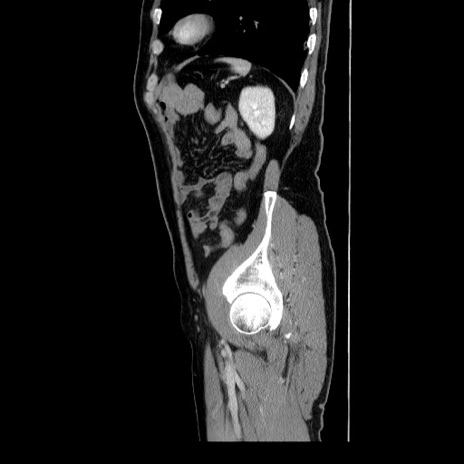

症例34(矢状断像)

【症例】60歳代 男性

【主訴】右鼠径部膨隆

【現病歴】1年程前より右鼠径部膨隆あり。自己にて還納可能だったため放置していた。3時間前より右鼠径部の脱出を認め、還納困難となり受診。

【既往歴】高血圧

【身体所見】右鼠径部に小児頭大の膨隆あり。弾性硬であり、用手還納は困難。左鼠径部にも膨隆を認める。脱出はなし。

【データ】WBC 15500、CRP 測定なし